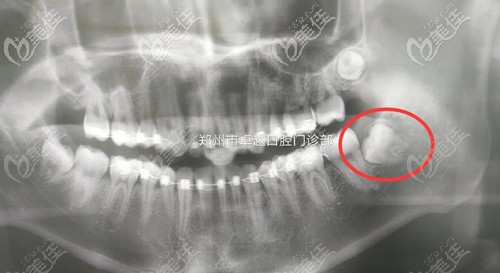

小伙們看,這是我的牙齒情況,整個(gè)智齒簡(jiǎn)直是睡在我的牙床里,這種長(zhǎng)相不規(guī)律有自己想法的牙齒一般都是阻生智齒,因?yàn)槲恢貌徽业难例X經(jīng)常發(fā)炎,而且還壓的我的大牙都歪斜了,所以這類(lèi)的牙齒別拖,趕緊拔掉!